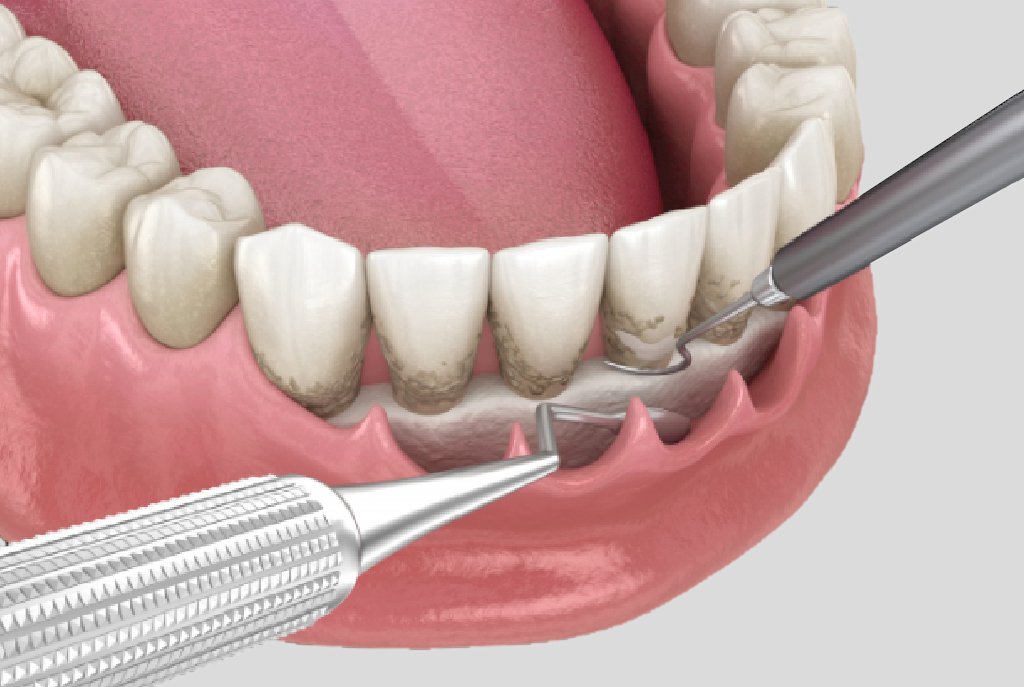

牙周病治療 – 非手術性治療

會以超音波洗牙機頭與牙周刮刀清除牙根表面的牙結石,並將牙根表面整

平,移除受感染的齒質讓牙周組織重新貼合乾淨的牙根表面。

清除牙結石與牙根整平